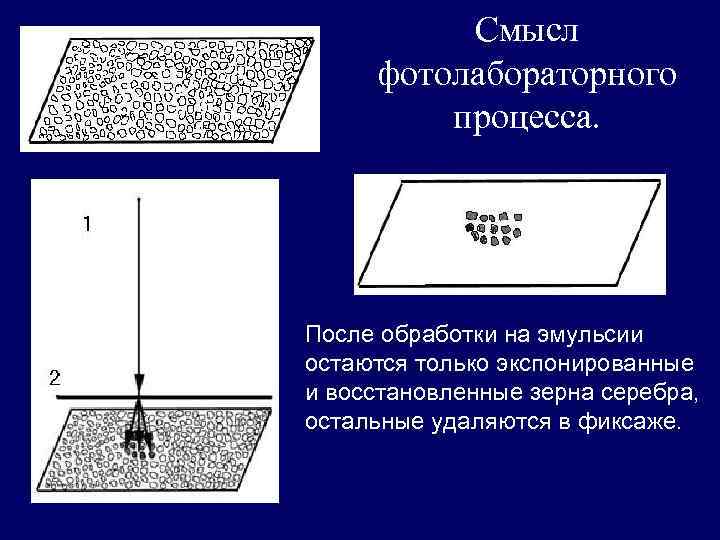

Формирование аналогового изображения Изображение формируется на рентгеновской пленке очень мелкими точками, оптическая плотность которых отражает степень поглощения объектом рентгеновского излучения.

Квант рентгеновского излучения (1) воздействует на зерна люминофора (2), вызывая их свечение. При рентгенологическом исследовании на зерна серебра происходит некоторое воздействие лучевой рентгеновской энергии, но в гораздо большей степени оказывает влияние свет от светящихся зерен слоя люминофора (2) усиливающего экрана.

Смысл фотолабораторного процесса. После обработки на эмульсии остаются только экспонированные и восстановленные зерна серебра, остальные удаляются в фиксаже.